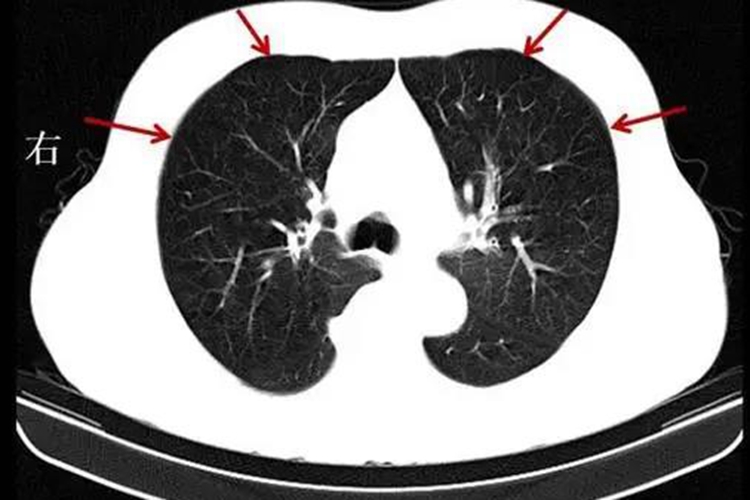

慢阻肺即慢性阻塞性肺疾病,以持续气流受限为特征,可表现为反复咳嗽、咳痰、气短、呼吸困难、喘息、胸闷等症状。

慢阻肺的病因通常可分为外因及内因。外因主要包括吸烟、职业性粉尘和化学物质吸入、空气污染、呼吸道感染等;内因主要与遗传、支气管哮喘和气道高反应性、肺脏发育不良等因素相关。